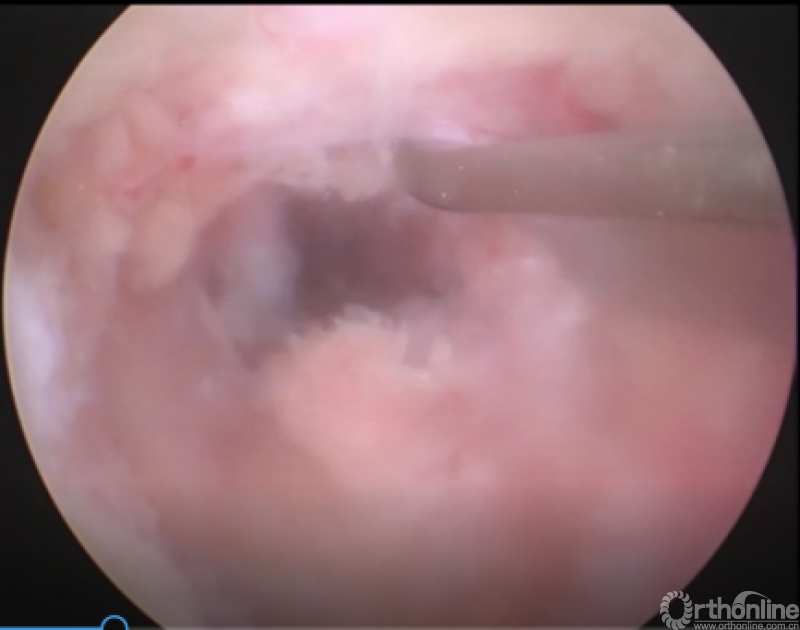

病例分享:(滑动查看)